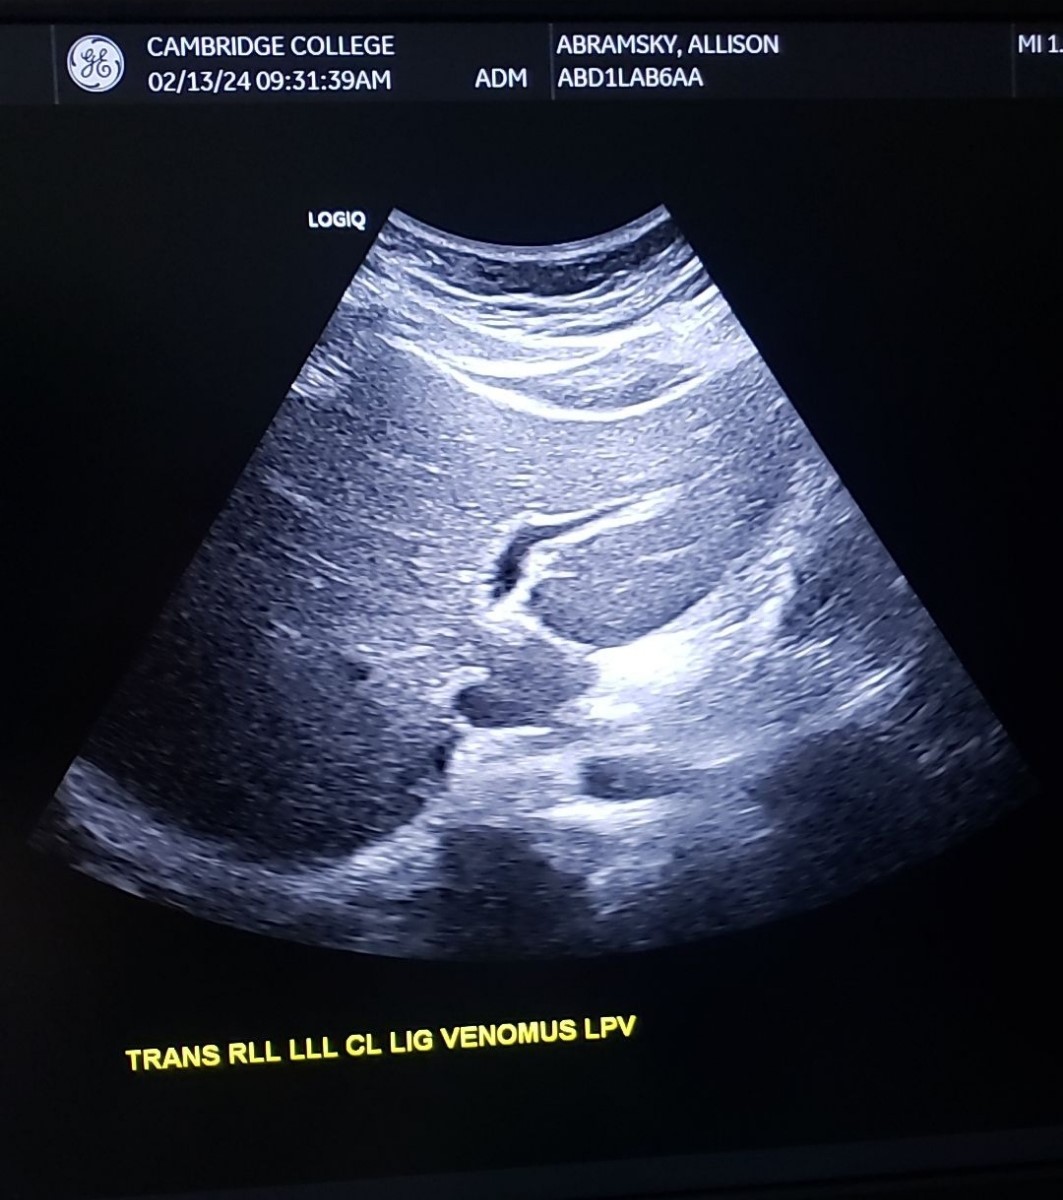

Trans LLL, RLL, CL (Lig. Venosum) & LPV

21